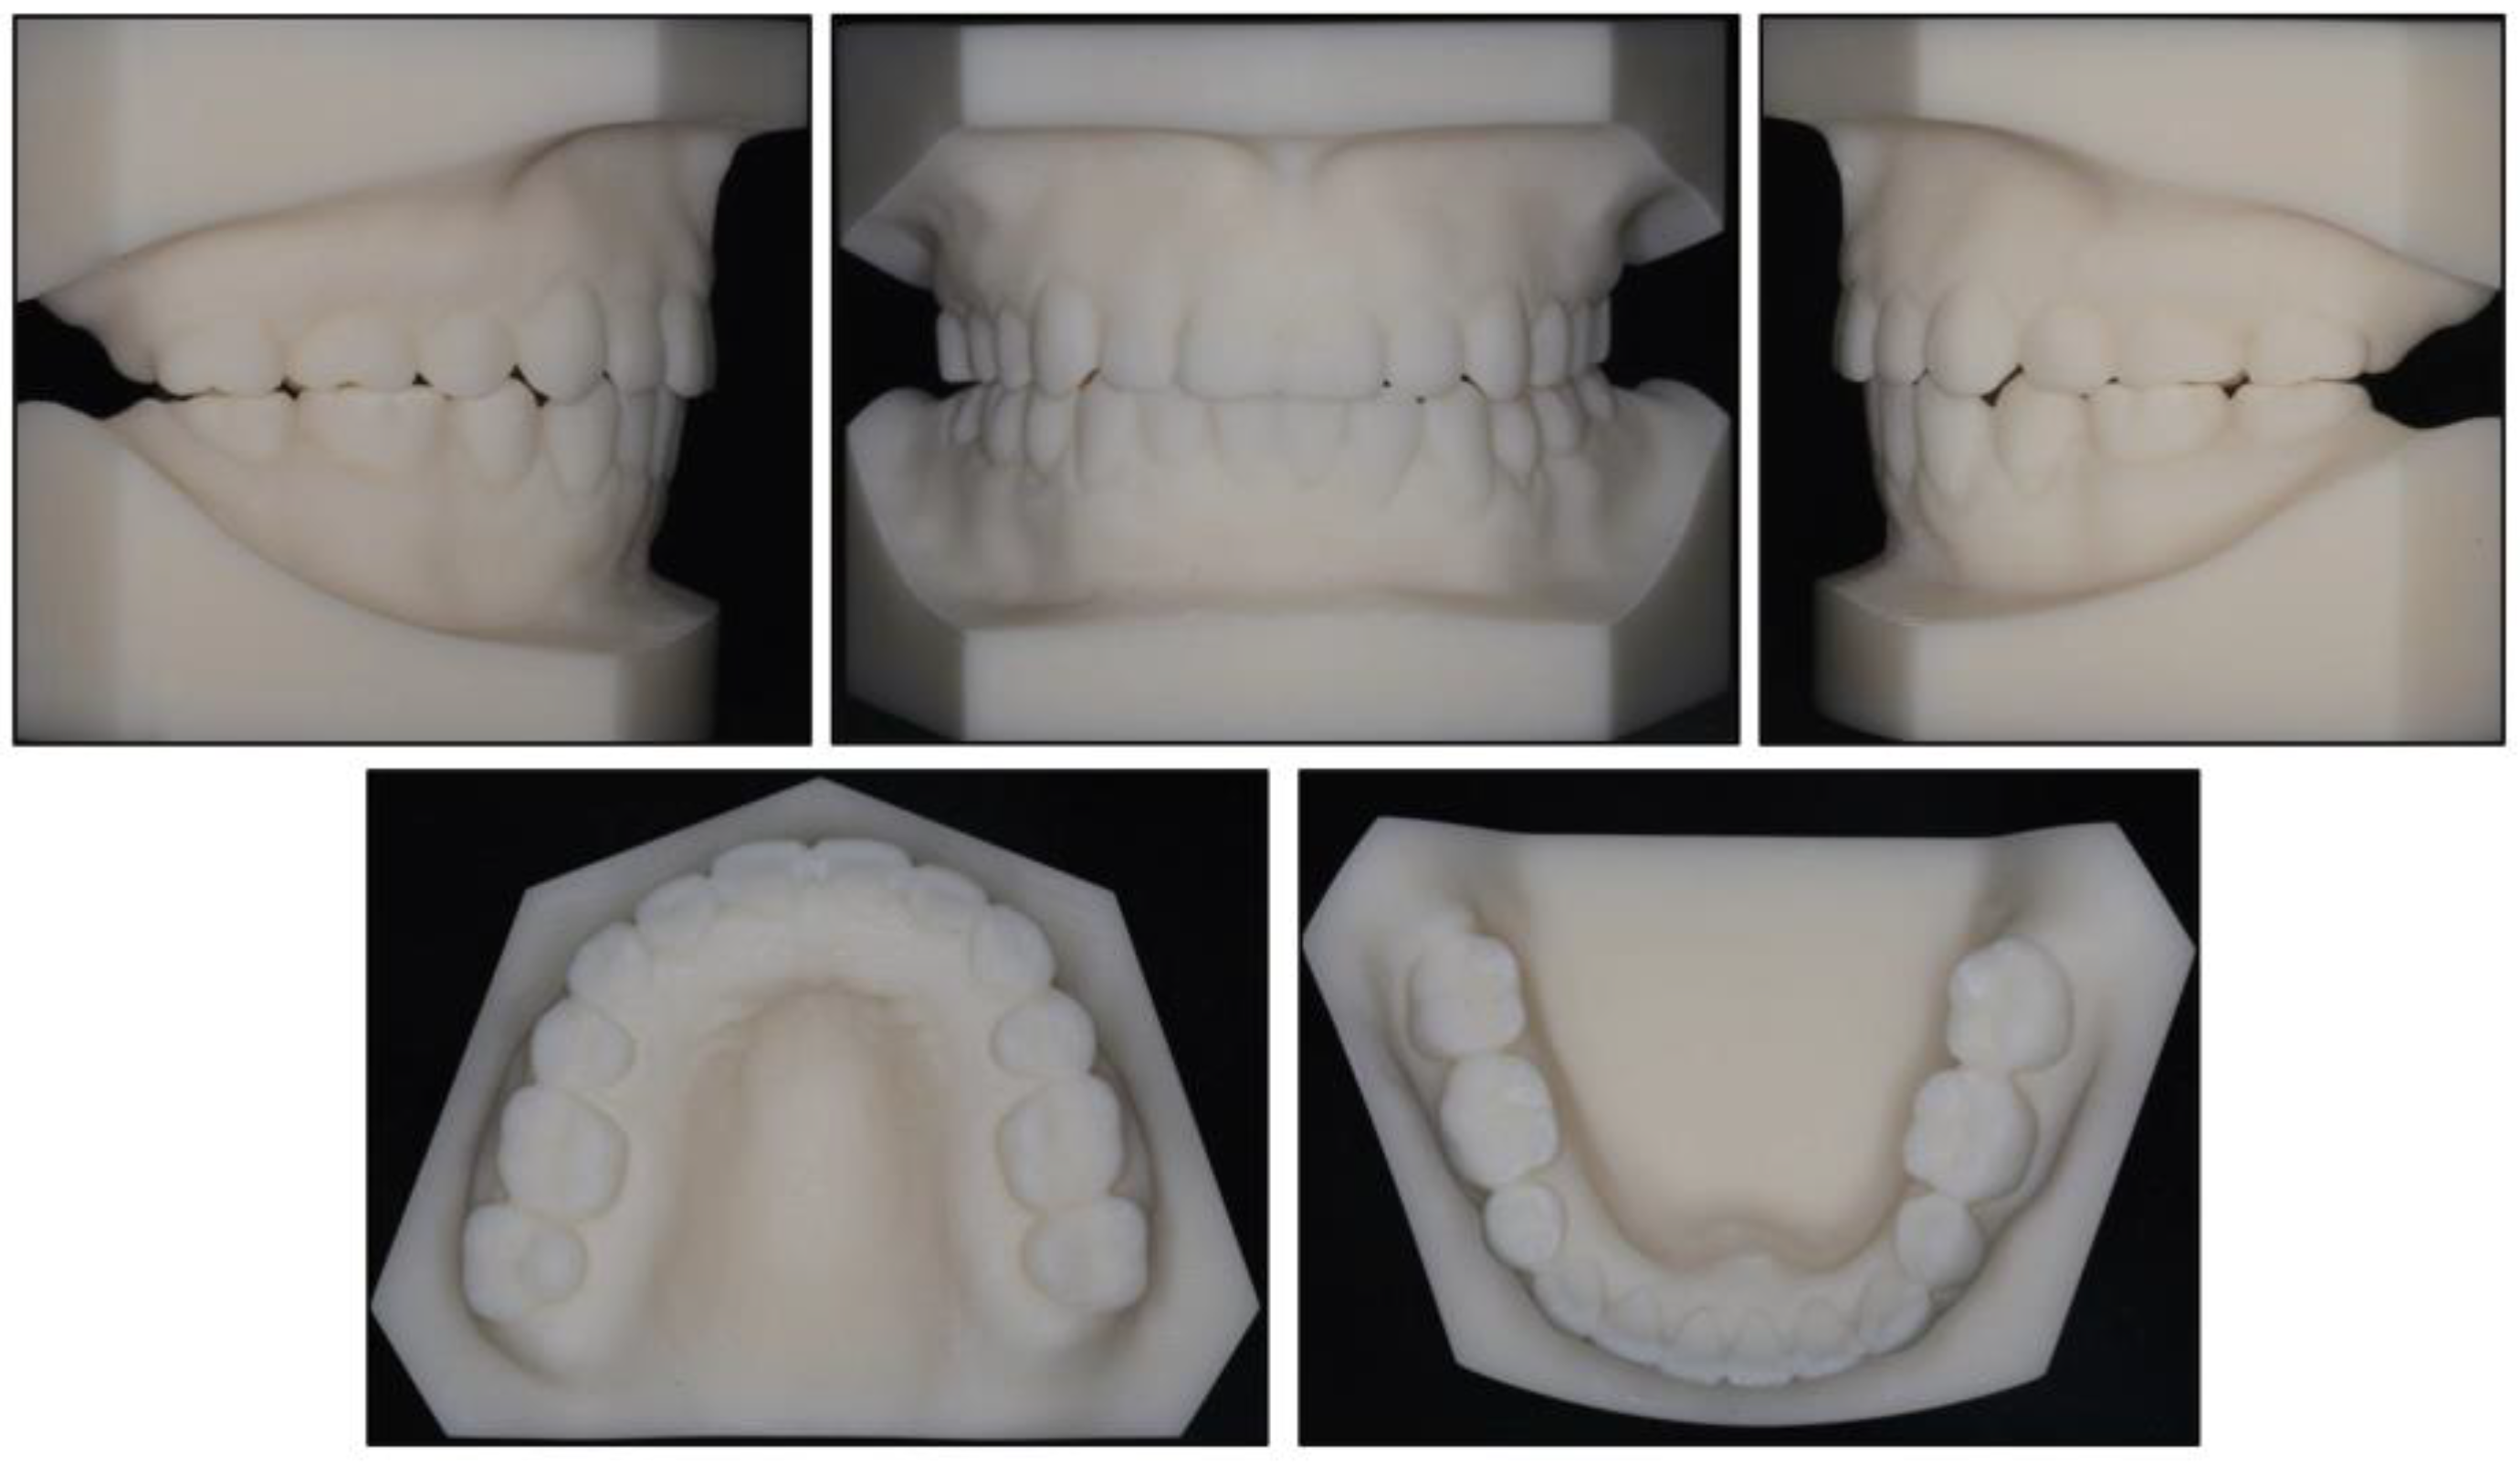

2.4. Treatment Progress

2.5. Treatment Results